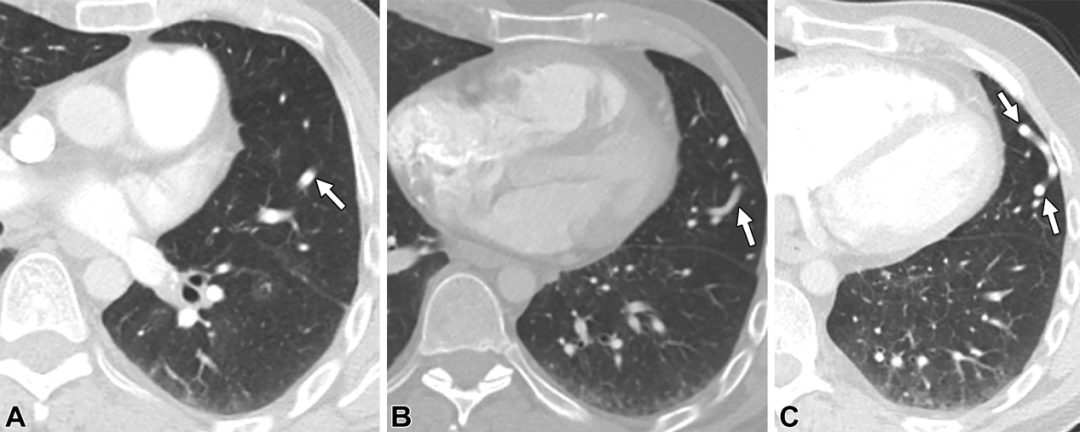

动脉动脉侧枝血管。48岁男性,有肺栓塞病史。轴位CT图,可见左肺上叶一个弯曲走行的血管结构(白色箭头),注意观察没有引流静脉或病灶。这一表现最符合继发于先前肺栓塞的动脉动脉侧枝血管形成。

肺动脉假性动脉瘤。56岁男性,既往Swan-Ganz导管置入史。(A)轴位平扫CT图,右肺上叶圆形结构(白色箭头)。(B)轴位增强CT图,圆形血管结构(白色箭头),注意观察没有引流静脉。(C)冠状位最大密度投影图,此结构与邻近的肺动脉相连(白色长箭头),符合肺动脉假性动脉瘤(白色短箭头)表现。